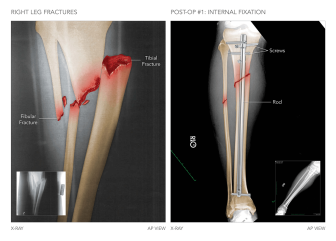

Summary of Left Leg Injuries